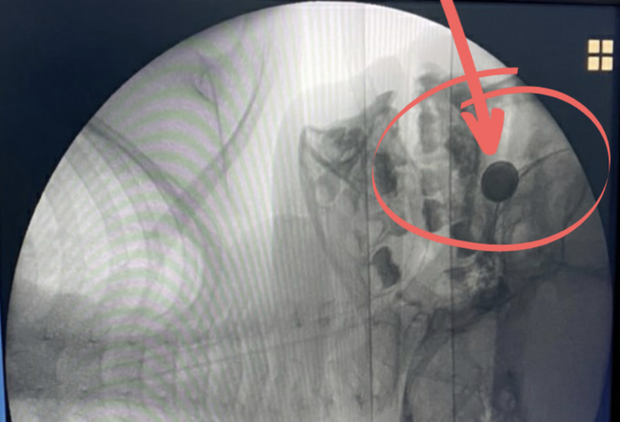

Cháu bé 4 tuổi suýt mất mạng vì lấy cục pin nhét vào mũi

Cháu bé tự chơi rồi tự nhét cục pin vào hốc mũi khiến máu chảy nhiều. Nghiêm trọng hơn, axit của pin đã nhanh chóng phá hủy hốc mũi và thành mũi.